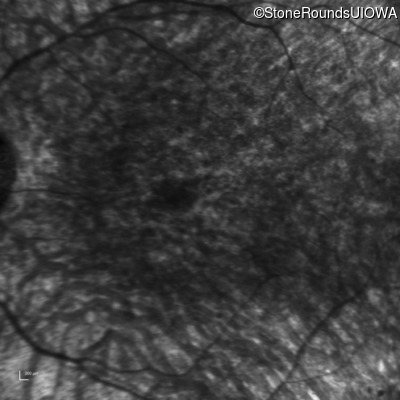

Infrared Fundus Photograph - Left - Hand Motion

Exemplar